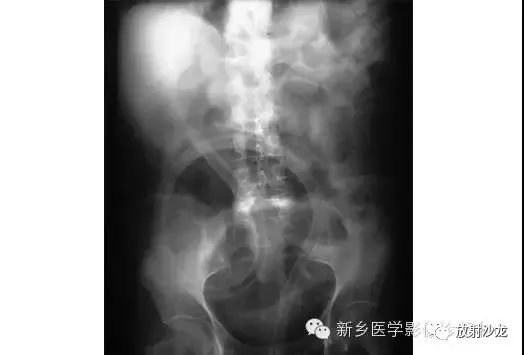

上图为9岁,腹痛、呕吐患儿所做的腹部平片。该患儿有阑尾炎合并腹膜炎病史。影像学异常是什么,最有可能的病因是什么?腹部X线片显示小肠襻的明显扩张、环状襞的消失,这与小肠梗阻的诊断相一致。该患儿既往有腹膜炎病史,梗阻是由腹腔粘连造成的。这个孩子最终经保守治疗康复。